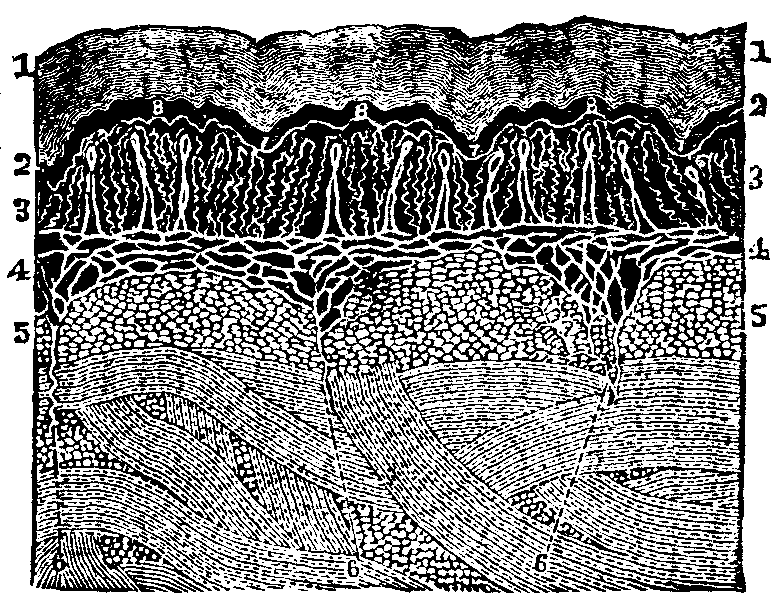

All living bodies are made up of tissues. There is no part, no organ,

however soft and yielding, or hard and resisting, which has not this

peculiarity of structure. The bones of animals, as well as their

flesh and fat, are composed of tissues, and all alike made up of cells.

When viewed under a microscope, each cell is seen to consist of three

distinct parts, a nucleolus, or dark spot, in the center of the

cell, around which lies a mass of granules, called the nucleus; and

this, in turn, is surrounded with a delicate, transparent membrane, termed

the envelope. Each of the granules composing the nucleus assimilates

nourishment, thereby growing into an independent cell, which possesses a

triple organization similar to that of its parent, and in like manner

reproduces other cells.

Fig. 4. Nucleated cell.

From Goeber. 1. Periphery of the cell, or cell-wall. 2. Nucleus. 3.

Nucleolus in the center.

A variety of tissues enters into the composition of an animal structure,

yet their differences are not always distinctly marked, since the

characteristics of some are not unlike those of others. We shall notice,

The Areolar, or Connective Tissue, is a complete network

of delicate fibers, spread over the body, and serves to bind the various

organs and parts together. The fibrous and serous tissues are modifications

20]The Nervous Tissue is of two kinds: The gray, which is

pulpy and granulated, and the white fibrous tissue. The Adipose

Tissue is an extremely thin membrane, composed of closed cells which

contain fat. It is found principally just beneath the skin, giving it a

smooth, plump appearance.

Fig. 5. Arrangement of

fibers in the Areolar Tissue. Magnified 135 diameters.

The Cartilaginous Tissue consists of nucleated cells, and, with

the exception of bone, is the hardest part of the animal frame. The

Osseous Tissue, or bone, is more compact and solid than the

cartilaginous, for it contains a greater quantity of lime. The Muscular

Tissue is composed of bundles of fibers, which are enclosed in a

cellular membrane.

Fig. 6. Human Adipose

Tissue.